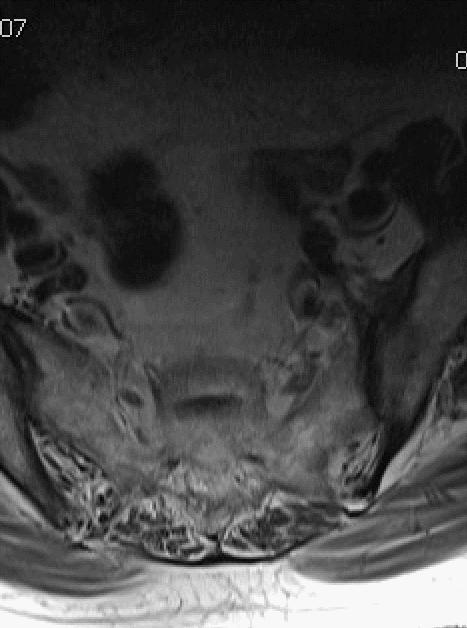

MRI平扫

如图所示,红色箭头可见不规则形异常信号,轴位呈哑铃型,病灶前缘侵及骶1、2椎体后缘,绿色箭头见骨质局部破坏,病灶T1低信号,T2稍高信号,压脂像明显高信号,信号尚均匀,腰4-5、腰5骶1椎间盘向后方突出,硬膜囊受压,蓝色箭头可见腰4-5椎间盘后缘纤维化小点状T2高信号,提示纤维环后缘撕裂。本例骶1-2椎间盘形成,骶1椎体腰化不完全。